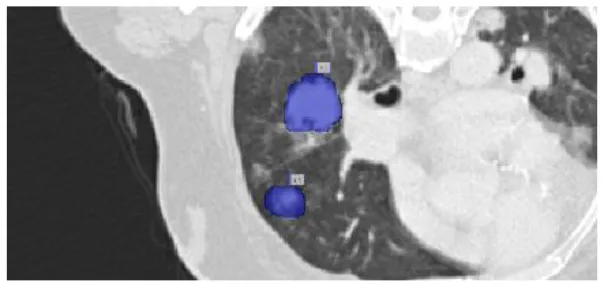

After preprocessing the image, shown in the Figure 11A the grouped picture, Figure 11B what was found when Lung tumors were identified. Figure 11C results of cutting lung tumors into whole pieces. Figure 11D the findings of the lung tumor search. Figure 11E picture showing the effects on a specific area of lung tumors when they are cut into pieces. Figure 11F a picture of a lung tumor that was accurately cut into pieces.

Figure 11

Utilizing the provided approach, we performed visual segmentation of heterogeneous lung nodules. (A) Clustered image. (B) Segmented image. (C) Extracted image. (D) Extracted image with nodules localizations. (E) Nodule capture. (F) Nodule region highlighted.